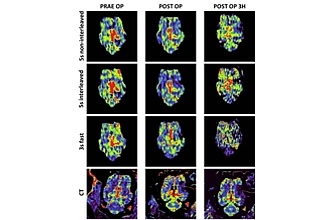

Der Fokus besteht in der Erforschung von röntgengestützten Applikationen in der interventionellen Neuroradiologie. Dabei sollen Innovationen in enger Kooperation zwischen SIEMENS und den Anwendern, d.h. der Medizin und Medizintechnik erarbeitet werden. Speziell sollen die Themenschwerpunkte der Messung der Gewebeperfusion mittels C-Arm CT an Angiographie-Systemen und der Integration von Mikroskopie in das Angiographie-Sytem bearbeitet werden.

Angiographie, C-arm, Neuroradiologie, Perfusion, Rekonstruktion